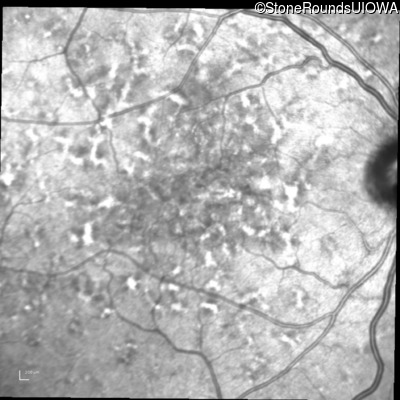

Fluorescein Angiography - Left - 20/40 +1 sc

Exemplar